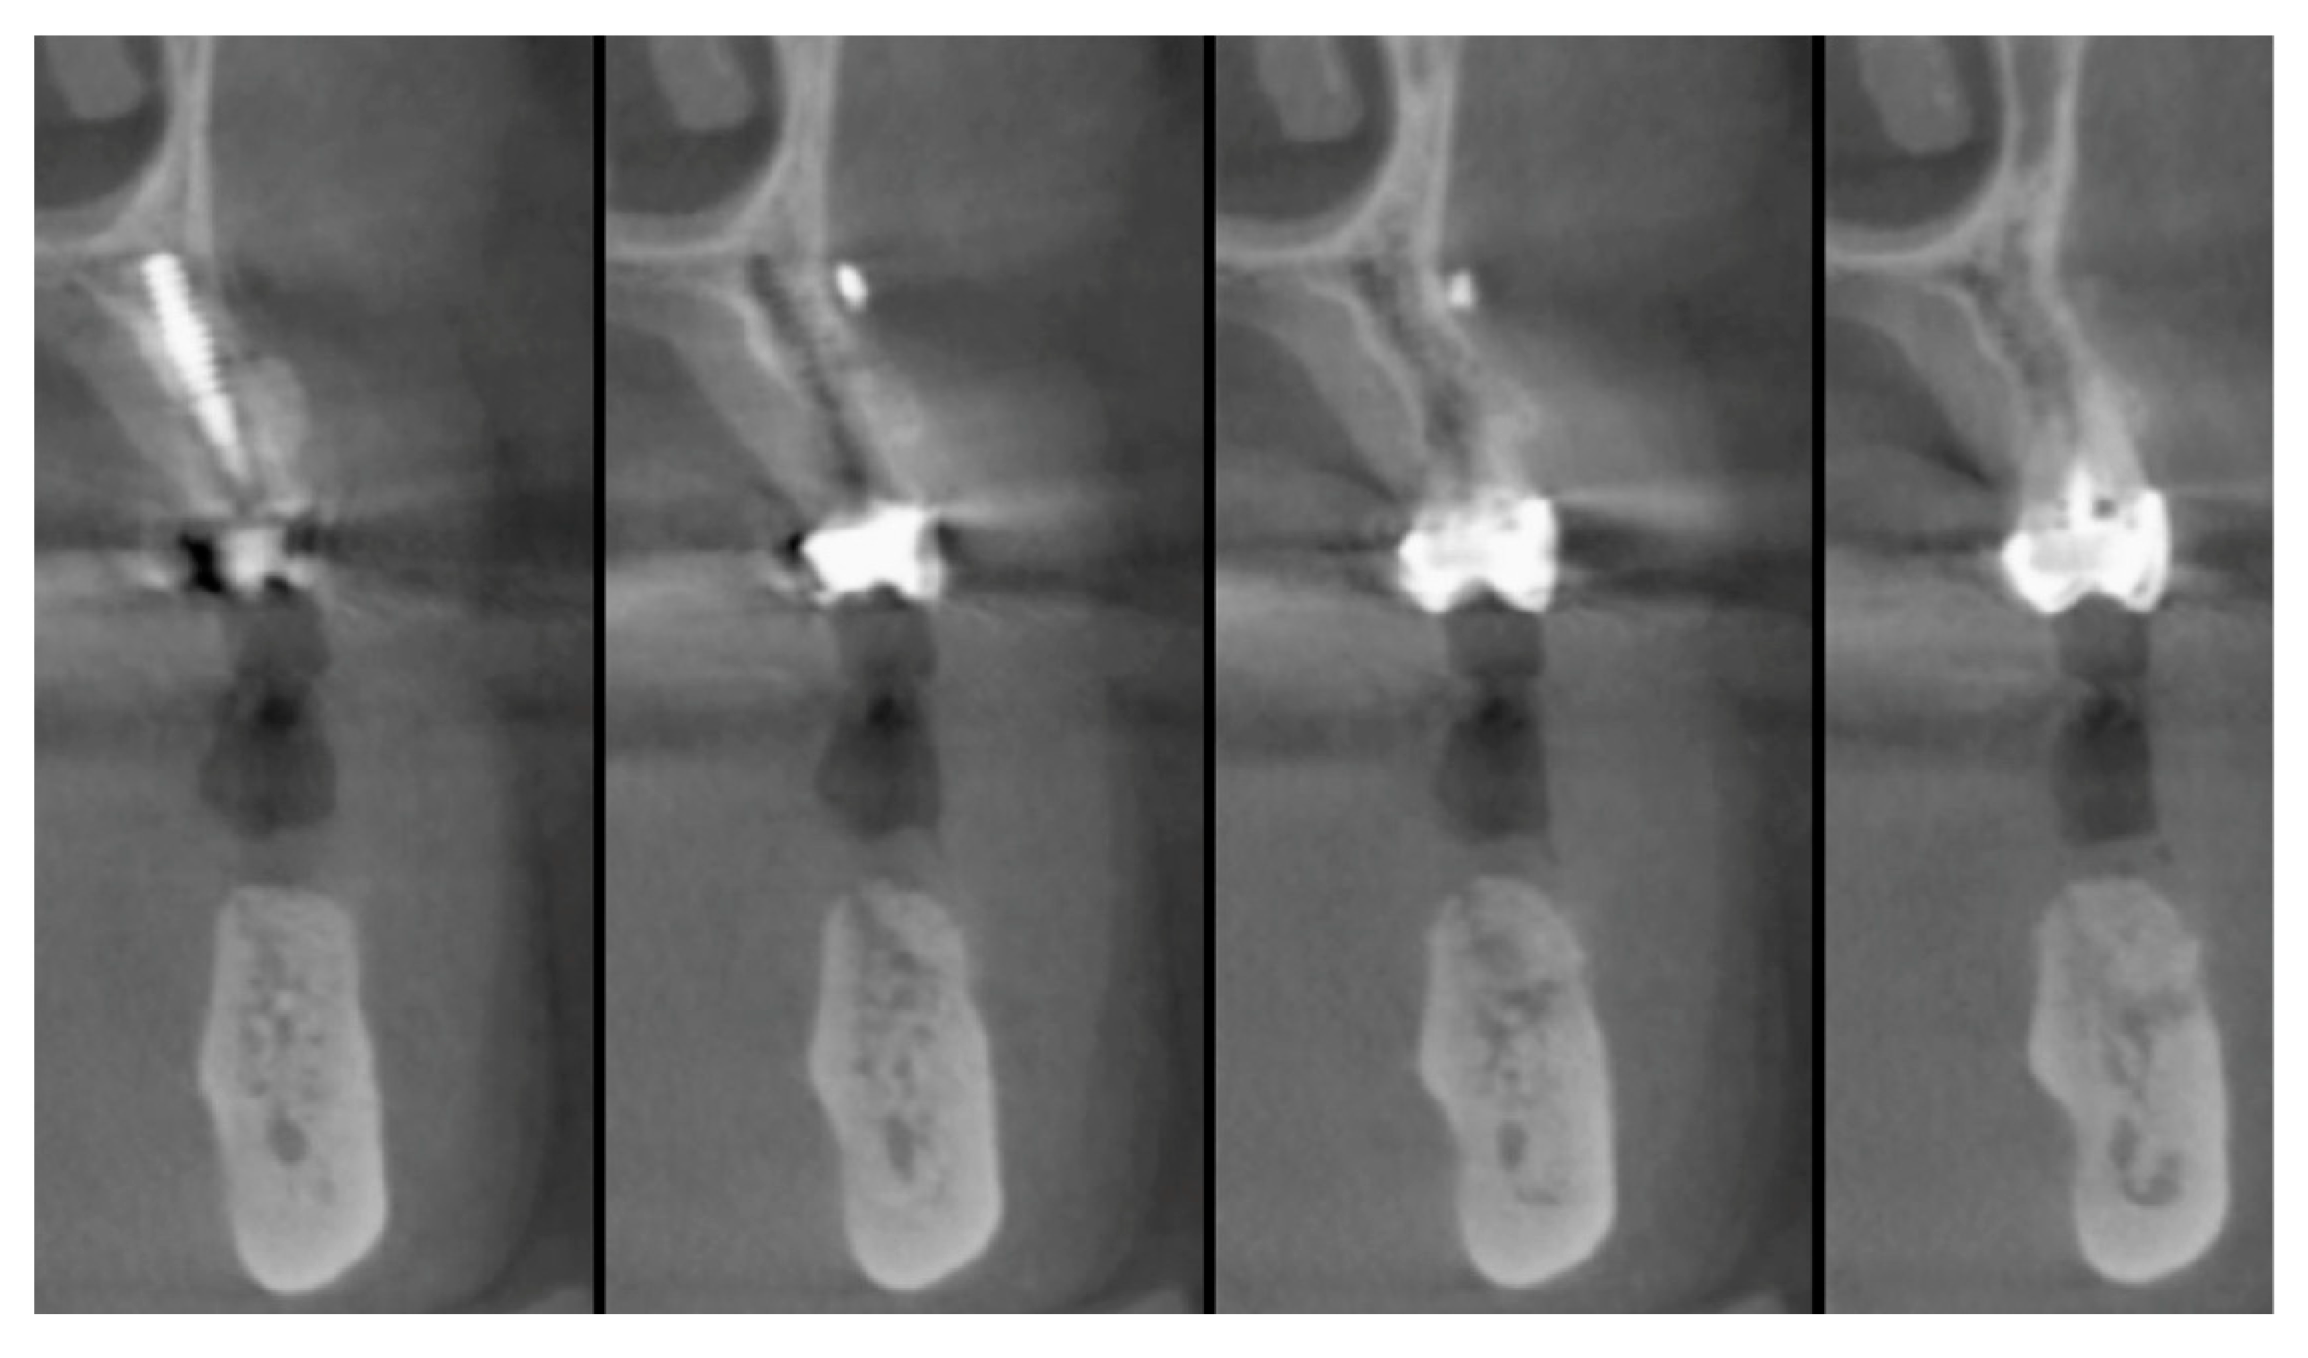

The faraway graft procedure follow up is 40 months and the near graft procedure follow up is 9 months (Average 24.5 months). The faraway implant follow up is 35 months and the near implant follow up is five months. The success rate of the tooth graft procedure is 99.1% (one site was infected and lost the regeneration and the implant) (Figure 6, Figure 7 and Figure 8). In all cases, after the all implants were inserted, complete osseointegration after proper healing period was achieved. After the healing period, hard and soft tissues were stable (Figure 9, Figure 10 and Figure 11). The healing of soft tissues after grafting procedures was particularly free of complications. The implant success rate was 98.94% (one implant failed).

Figure 9. Reopening after three months.

Figure 10. Implant placement in the regenerated bone after three months.

Figure 11. Prosthesis and 19-months of follow-up.